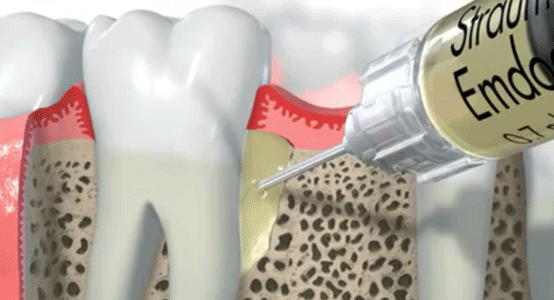

Often if periodontal disease (gum disease) is not treated in time it leads to the loss of material from the bone supporting the teeth. When the resulting bone defect is localised, we can treat it with Emdogain™ in an attempt to regenerate the bone and to recover the force supporting the teeth.

Emdogain™ is a derivative of enamel matrix proteins proven to help regenerate the tissues surrounding teeth (root cement, bone, and periodontal ligament).

With Emdogain™ it is possible to reliably regenerate bone lost due to periodontitis, helping to preserve strong teeth